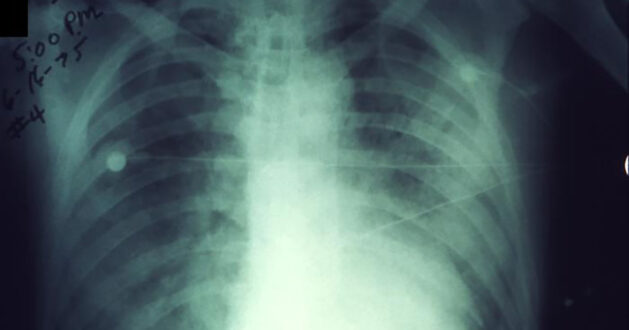

Pnömonik veba en ciddi ve kişiden kişiye bulaşabilen tek formdur. Bulaşıcı damlacıkların solunmasıyla ya da tedavi edilmemiş bubonik veya septisemik vebadan gelişebilir.

Pnömonik vebalı kişilerde ateş, baş ağrısı, halsizlik ve nefes darlığı, göğüs ağrısı, bazen sulu veya kanlı mukus ile hızla gelişen pnömoni görülür.